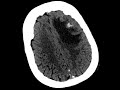

Anaplastic Oligodendroglioma

There is an avidly enhancing heterogeneous mass centered in the cortex and subcortical white matter of the left middle and inferior frontal gyri with moderate perilesional edema resulting in mild effacement of the left lateral ventricle and mild rightward midline shift. The CT shows that there is a small area of calcification. The differential diagnosis includes metastasis, oligodendroglioma, and high grade astrocytoma. For a partially calcified frontal lobe mass involving the cortex and subcortical white matter, the best diagnosis is oligodendroglioma which was confirmed on pathology. Enhancement is more common in anaplastic oligodendrogliomas which have a poorer prognosis as was seen in this case.